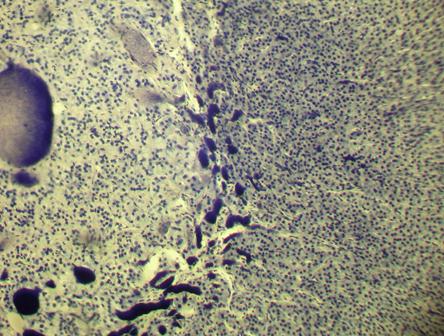

Фото. 3.4.1. Надпочечник. Железный гем.

Малое увеличение. (Ув.10х7)

Фото. 3.4.5. Сетчатая зона коры и мозговое вещество надпочечника. Железный гем.

Среднее увеличение. (Ув.20х7)

| гемокапилляры сетчатой зоны коркового вещества | |

| синусоидные капилляры мозгового вещества | |